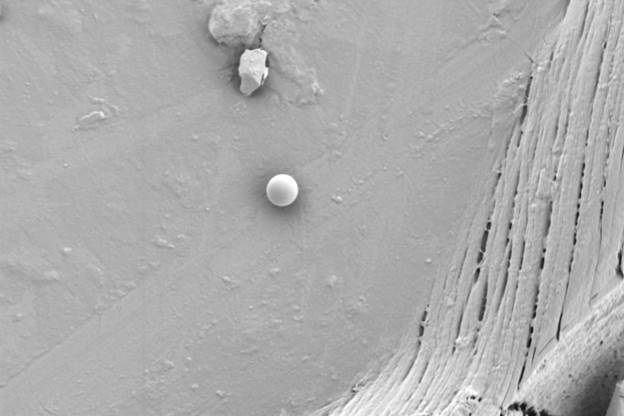

Так, при плановой проверке качества капсул с сульфатом глюкозамина с помощью оптического микроскопа были обнаружены мелкие дефекты на поверхности. Последующий анализ на СЭМ при высоком увеличении выявил микротрещины и прикрепленные пластинчатые частицы неправильной формы (рис. 1а). Морфология трещин указывала на их возможное происхождение в результате коррозии под напряжением, связанной с неравномерной сушкой покрытия и релаксацией полимерных напряжений. Инородные частицы по своей структуре (рис. 1b — чистая поверхность) отличались от матрицы капсулы.

Сопоставление с типичными микроорганизмами позволило исключить биологическую природу загрязнения; наиболее вероятным источником была признана неорганическая пыль из производственной среды или вспомогательных веществ. Эти данные послужили основой для корректировки режимов нанесения покрытия и ужесточения контроля чистоты в производственных помещениях.

Рис. 1b — Фрагмент неповрежденной поверхности капсулы (без загрязнений). Изображение получено с помощью LANSEM 30.